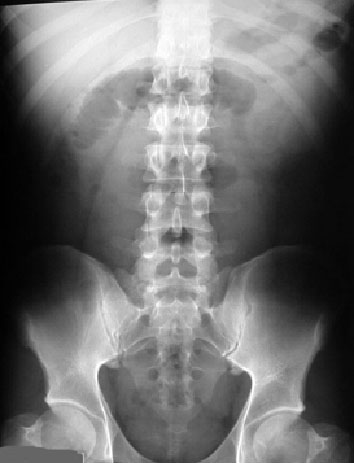

SIGNO DE LA LÍNEA DEL PSOAS o SIGNO DEL PSOAS

La presencia, ausencia o atenuación del perfil del músculo psoas en la radiografía simple de abdomen, o bien la diferencia en el aspecto de las dos líneas del psoas, se ha utilizado en el diagnóstico diferencial de la patología intraabdominal y la retroperitoneal. El borramiento de la línea del psoas se ha descrito en pacientes con procesos en los que se altera la radiotransparencia del tejido adiposo retroperitoneal (infiltración por sangre, edema, líquido o tumoración).

Sin embargo, la línea del psoas puede no verse en hasta un 40 % de sujetos normales y, al contrario, puede estar conservada la línea en presencia de patología retroperitoneal, por lo que su utilidad es muy escasa.

Lo incluimos aquí por ser un signo clásico muy difundido fuera del ámbito radiológico.